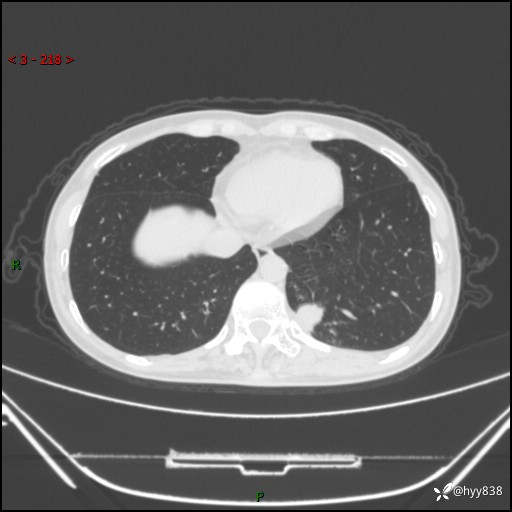

胸部CT平扫

增强动脉期+静脉期

各期CT值:48hu 65hu 76hu